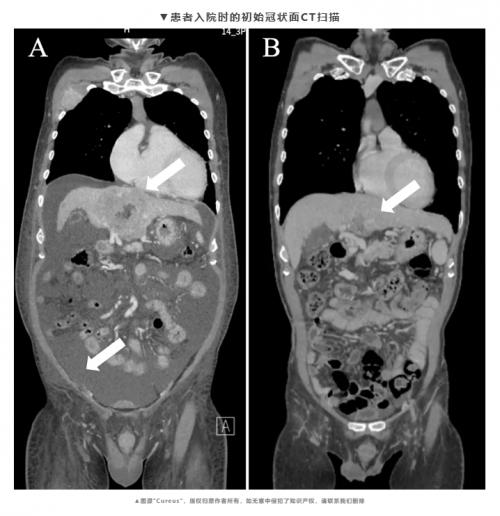

(一)晚期肝癌:9.3cm巨瘤缩小至可手术,实现根治

58岁赵先生确诊局部晚期肝癌,9.3cm肿瘤伴肝内多发转移,无手术机会。采用“肝动脉灌注化疗+ZMPB-NK006”方案,依托其现货优势,介入治疗3天后即完成首次回输,仅出现轻微乏力,耐受性远超传统治疗。4周期后,原发瘤缩至3.7cm,转移灶基本消失,成功接受根治术,术后3疗程巩固治疗。随访15个月无瘤生存,肝功能及生活质量恢复正常,疗效与Ⅰ期临床数据(客观缓解率63.6%,中位总生存期41.6个月)高度吻合。